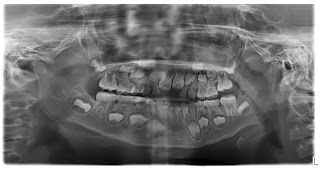

做媽媽的我當然想知道昕昕牙科全而情況,加上牙齒姐姐都明白我的擔憂,所以安排昕昕的牙齒照X光,價錢係$400,能夠全部牙睇曬收呢個價錢真係好過之前俾$120照幾隻牙仔~~~

依家的牙齒X光片係可以電腦輸出,檢查後數天可以電郵收到,昕昕在照X光時有少少郁,所以部份位置矇咗D,好在冇影響我們睇佢的情況~~~

牙醫姐姐話昕昕的恆齒大都已經在準備,門牙沒有牙腳紮根,所以不用擔心門牙唔會出來,牙醫姐姐仲安排昕昕兩個月後再檢查進度~~~

牙醫姐姐話昕昕的十四歲齒也在裡面,諗起我自己在17歲就出了智慧齒,莫非昕昕似我會早出大牙o(*≧▽≦)ツ